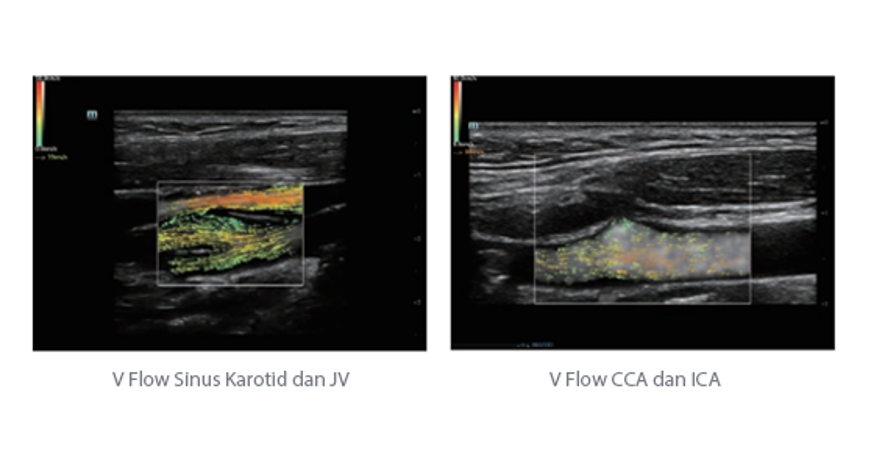

Selain kualitas gambar premium, Resona 7 juga meningkatkan kemampuan penelitian klinis dengan V Flow revolusioner untuk evaluasi hemodinamika vaskular, serta pengambilan penampang tercanggih dari rangkaian data 3D untuk diagnosis CNS pada janin. Kombinasi pengoperasian multisentuh berbasis gerakan yang paling intuitif dengan semua fitur klinis penting membuat Resona 7 menjadi gebrakan baru dalam inovasi ultrasound.